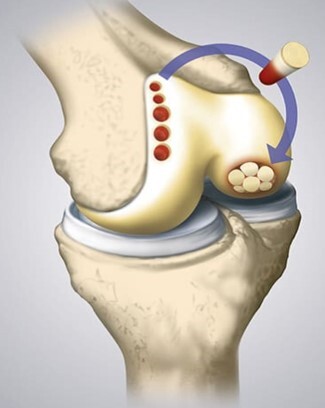

8

Tx and pearls

Treatment:

Kids: more conservative tx like rest, cast, NWB x several months

Adults: stable – weight bearing restrictions, unstable surgical repair – drilling, screw fixation, resurfacing, joint replacement

Both require surgical removal if there is a loose body in the joint

Pearls:

Most common location of OCD in the knee is the posterior lateral aspect of the medial femoral condyle (70%), capitellum of humerus, talus